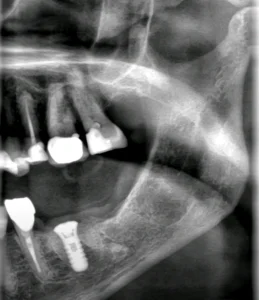

Ett nyligen utfört fall i vår klinik gällde extraktion av tand 36 (första molaren i underkäken), där vi direkt kunde placera ett implantat i samma kirurgiska seans. Resultatet blev stabilt, vävnadsbevarande och estetiskt tilltalande. Denna typ av behandling har visat sig mycket effektiv, förutsatt att rätt indikationer föreligger och att alla steg i behandlingen genomförs med kirurgisk precision.

Fall: Extraktion och direktimplantat i tand 36

I det aktuella fallet extraherades en kraftigt karierad och frakturerad tand 36. Trots viss infektion i området kunde vi efter noggrann rengöring och antibakteriell behandling placera ett implantat med utmärkt primär stabilitet (över 45 Ncm). Vi använde en flappfri teknik för att bevara blodförsörjningen till tandköttet och fyllde defekten med xenograft samt PRF.

Patienten återkom för uppföljning efter två veckor med god läkning och utan postoperativa komplikationer. Efter cirka tre månader planeras avtryck och slutlig protetik.